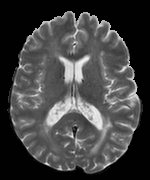

We observed that memberships predicted with an FC layer result in more false positives compared to a fully convolutional network. An example is shown in Fig. 2, where lesion memberships are generated from MPRAGE and FLAIR using the proposed model of convolutional pathways and a comparable model where the last convolutional pathway after concatenation (see Fig. 1) is replaced with a FC layer predicting voxel-wise memberships. The membership image generated with an FC layer, although being close to inside the lesions, has high values () in the left and right frontal cortex where the FLAIR image shows some artifacts. However, the membership obtained with the proposed method shows relatively low values near the frontal cortex.

With FC layer, voxel-wise predictions are performed for each voxel on a new image. Therefore the prediction time for the whole image comprising millions of voxels can take some time even on a GPU, as mentioned in Wachinger et al. (2017). In contrast, with fully convolutional prediction, lesion membership estimation of a mm3 MR volume of size takes only a couple of seconds. Note that although patches are used for training, the final trained model contains only convolution filters and does not depend in any way on the input patch size. Therefore during testing, the lesion membership of a whole 2D slice, irrespective of the slice size, is predicted at a time by applying convolutions on the whole slice. Without an FC layer, the images need not be decomposed into sub-regions, e.g., Kamnitsas et al. (2017). Consequently, there is no need to employ membership smoothing between sub-regions. In addition, since the training memberships, generated by Gaussian blurring of hard segmentations, are smooth, the resultant predicted memberships are also smooth (Fig. 2 last column).